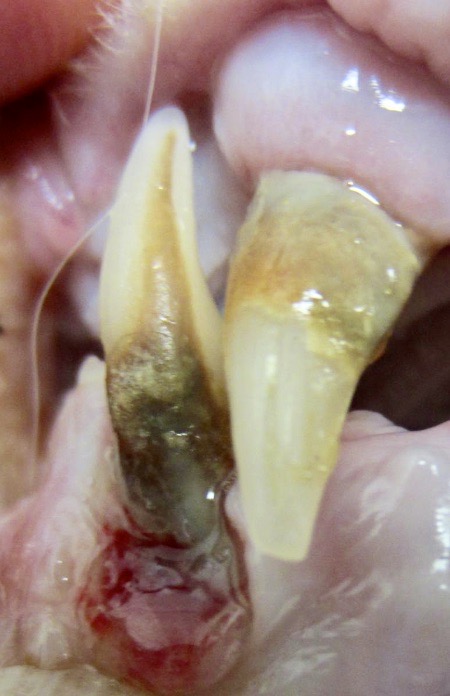

Après la gencive, le parodonte : sur la photo de gauche, qui montre les canines supérieure et inférieure d’un chat, on observe un décollement et une rétraction de la gencive autour du croc du bas, (croc ou canine, c’est pareil), qui laissent une bonne partie de la racine à nu. Tout en bas, on devine l’existence d’une poche entre gencive enflammée et racine, de laquelle s’écoule du pus. Encore un peu de patience, et la dent tombera toute seule… à moins qu’on ne l’aide un peu, ce qui est, de toute façon, tout ce qu’on peut encore faire pour elle. Le croc du haut est en train de suivre le même chemin, avec un temps de retard. Sur la photo de droite, on observe le décollement et la rétraction de la gencive, constituant ainsi une poche autour des racines de la dernière prémolaire supérieure, chez un chat infecté par le FIV : les bactéries se font déjà une joie de s’y multiplier, produisant des toxines à l’origine de la destruction de l’os alvéolaire, et de la résorption du collet dentaire (voir ci-dessous).

Et puis, particularité du chat : dans cette espèce, il n’y a pas que le parodonte qui est attaqué : la dent aussi, avec une résorption des tissus dentaires conduisant à la formation de véritables cavités creusées dans le cément, puis la dentine de la dent : ce sont les lésions de résorption du collet, ou « neck lesions » des anglo-saxons. Evidemment, la dent ainsi fragilisée finit souvent par se casser… et là, inutile de dire que ça fait mal ! Vous imaginez, la super-carie ? Aïe aïe aïe !